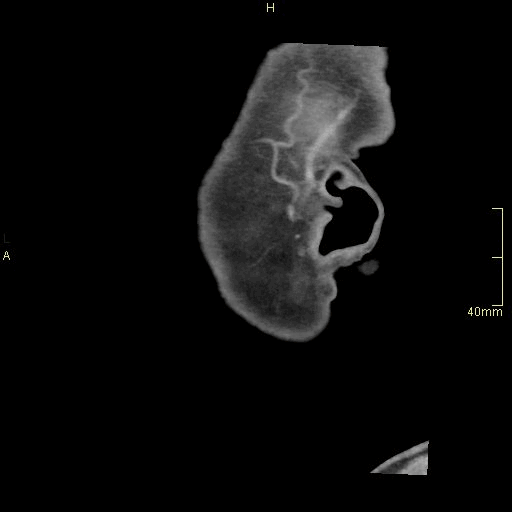

CT Facial Bones/Sinuses Contrast- Soft Tissue window (sagittal)

CT Facial Bones/Sinuses Contrast- Bone window (sagittal)